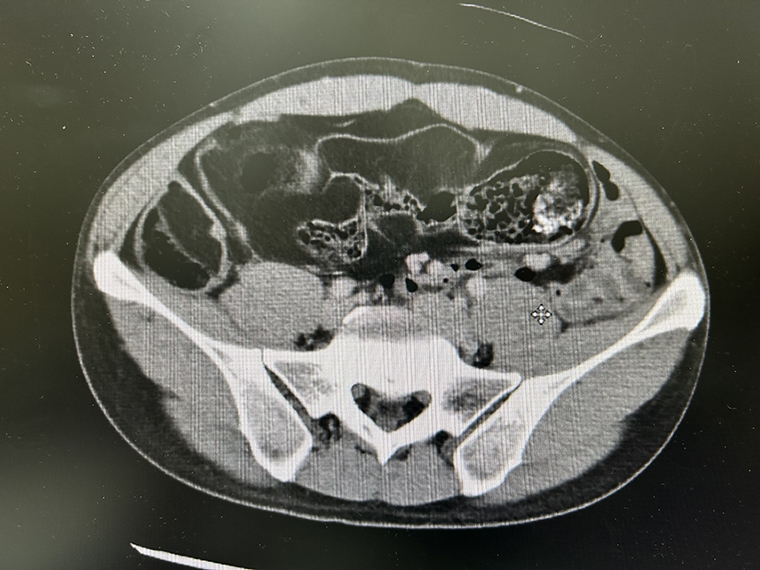

該名男性患者因長期腹脹至外院就診,初步大腸鏡檢查未見明顯異常,但醫師於右下腹觸診發現約5公分腫塊,轉診至本院進一步檢查。經台北中山醫院胃腸肝膽科主任吳德強醫師安排電腦斷層掃描,發現腹腔內多處低回音腫塊,並合併嚴重腸道糞便滯留,初步懷疑為「惡性腹腔脂肪肉瘤」,經多專科團隊會診後,決定採剖腹探查。

▲患者腹部右側及中間部位布滿多發性脂肪瘤,腹部中部除小腸外還有一大型憩室。(圖/台北中山醫院提供)

手術中發現患者末端小腸嚴重糾結,腸腔內填滿脂肪樣腫瘤與軟便,並合併數十處大小不一的腸憩室。經歷3小時以上精細剝離與切除,成功清除總重達2.5公斤的病變組織。病理報告診斷為:「多發性脂肪瘤性息肉性腫瘤合併多發性憩室與部分腸阻塞」,此類病變多數見於大腸,且腫瘤數量有限,但該患者病灶集中於小腸末端,腫瘤數量近百,極為罕見。